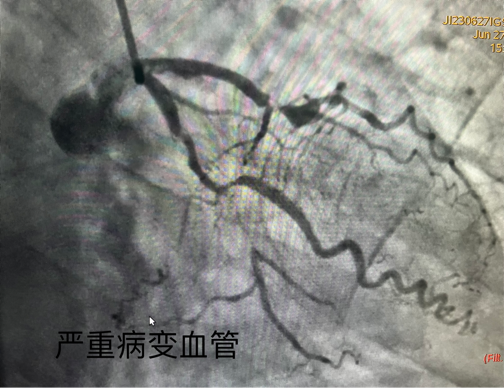

2. 对于血管急性闭塞的患者,术者通常会首先打开闭塞的血管,在犯罪血管放支架。这个时候即使还剩另外一支严重的病变血管,也需要下台,建议患者分次治疗。

3. 对于弥漫病变,分叉病变,尤其是多支病变,双侧同时都有严重的病变,一次做完多支血管的话一是患者耐受不了,二则血管处理好了以后需要时间恢复。只能先处理一侧,病情稳定后再处理另一侧的血管。